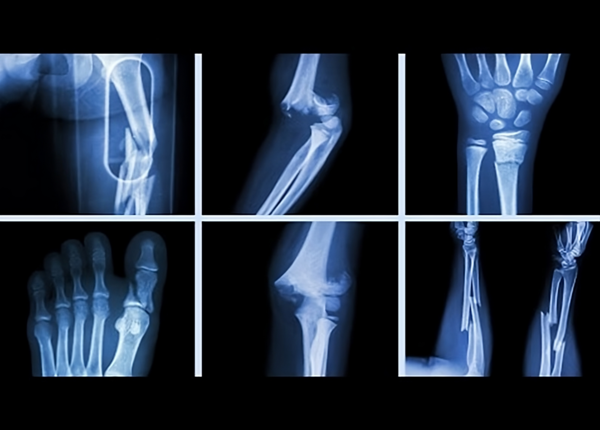

Gãy xương là hiện tượng tổn thương cấu trúc bình thường của xương, xảy ra khi lực tác động vượt quá khả năng đàn hồi và chịu lực của xương. Sự gãy có thể ở mức độ nhẹ như rạn xương, nứt xương cho đến gãy hoàn toàn, gãy nhiều đoạn hoặc gãy kèm theo di lệch. Gãy xương được phân loại dựa trên nhiều yếu tố như hình thái gãy (thẳng, xoắn, chéo…), vị trí gãy (đầu xương, thân xương), mức độ tổn thương (gãy kín hay gãy hở), hoặc có kèm theo biến chứng hay không.

Gãy xương là tình trạng phá vỡ cấu trúc giải phẫu của xương do lực tác động mạnh hoặc bệnh lý